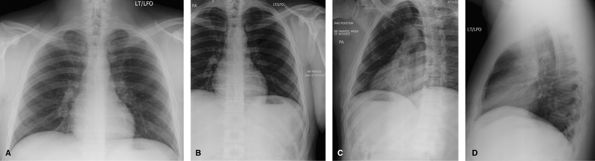

Bony Thorax

For most acute rib injuries, the protocol is a PA erect

chest exam to evaluate for pneumothorax. Only patients with pathological

fractures or patients who have undergone a bone scan should be imaged

for rib fractures. Legal cases may also require documentation of

fracture. It is important to have a “bb” at the site of pain and for the

technologist to annotate if the bb is anterior or posterior.

![]() |

|

Figure 63 PA chest only. If history is acute rib injury.

Figure 64 Post bone scan or pathological fractures. (A) AP or PA ribs—dependent on site of injury. (B, C) Affected side closest to Bucky oblique ribs.